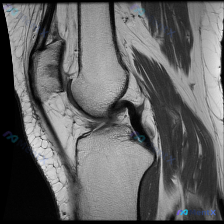

这是一份单张膝关节矢状位T1加权MRI影像,临床提出的核心观察方向是「软骨异常」,无其他临床病史、症状或其他检查资料。

- 骨骼: 股骨远端、胫骨近端、髌骨骨髓信号均匀,骨皮质完整,没有局灶信号异常、骨质缺损或皮质中断

- 关节软骨: 股骨滑车面、胫骨平台关节软骨轮廓清晰,没有局灶性变薄或信号异常增高

- 半月板、交叉韧带: 所见层面内半月板形态信号正常,前后交叉韧带连续,走行信号都正常

- 肌腱、滑囊、其他软组织: 髌腱、股四头肌腱信号正常,髌上囊、关节腔没有异常积液,腘窝没有占位,髌下脂肪垫信号均匀

整体评估:这一个层面的T1加权影像,没有看到明确的骨质、软骨、韧带或软组织异常,也没有急性创伤或慢性退行性改变的典型征象。